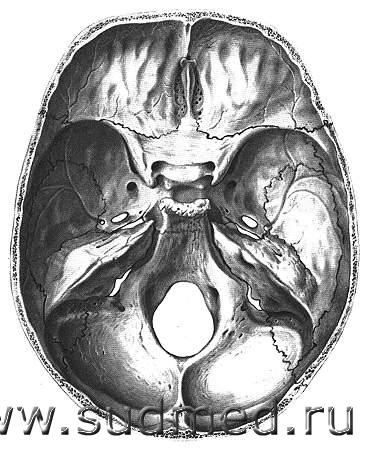

Если по-обывательски и совсем уж просто сказать - это та часть черепа, на которой головной мозг лежит. smile.gif

Эскизы прикрепленных изображений

Судебная медицина - Прикрепленное изображение Судебная медицина - Прикрепленное изображение